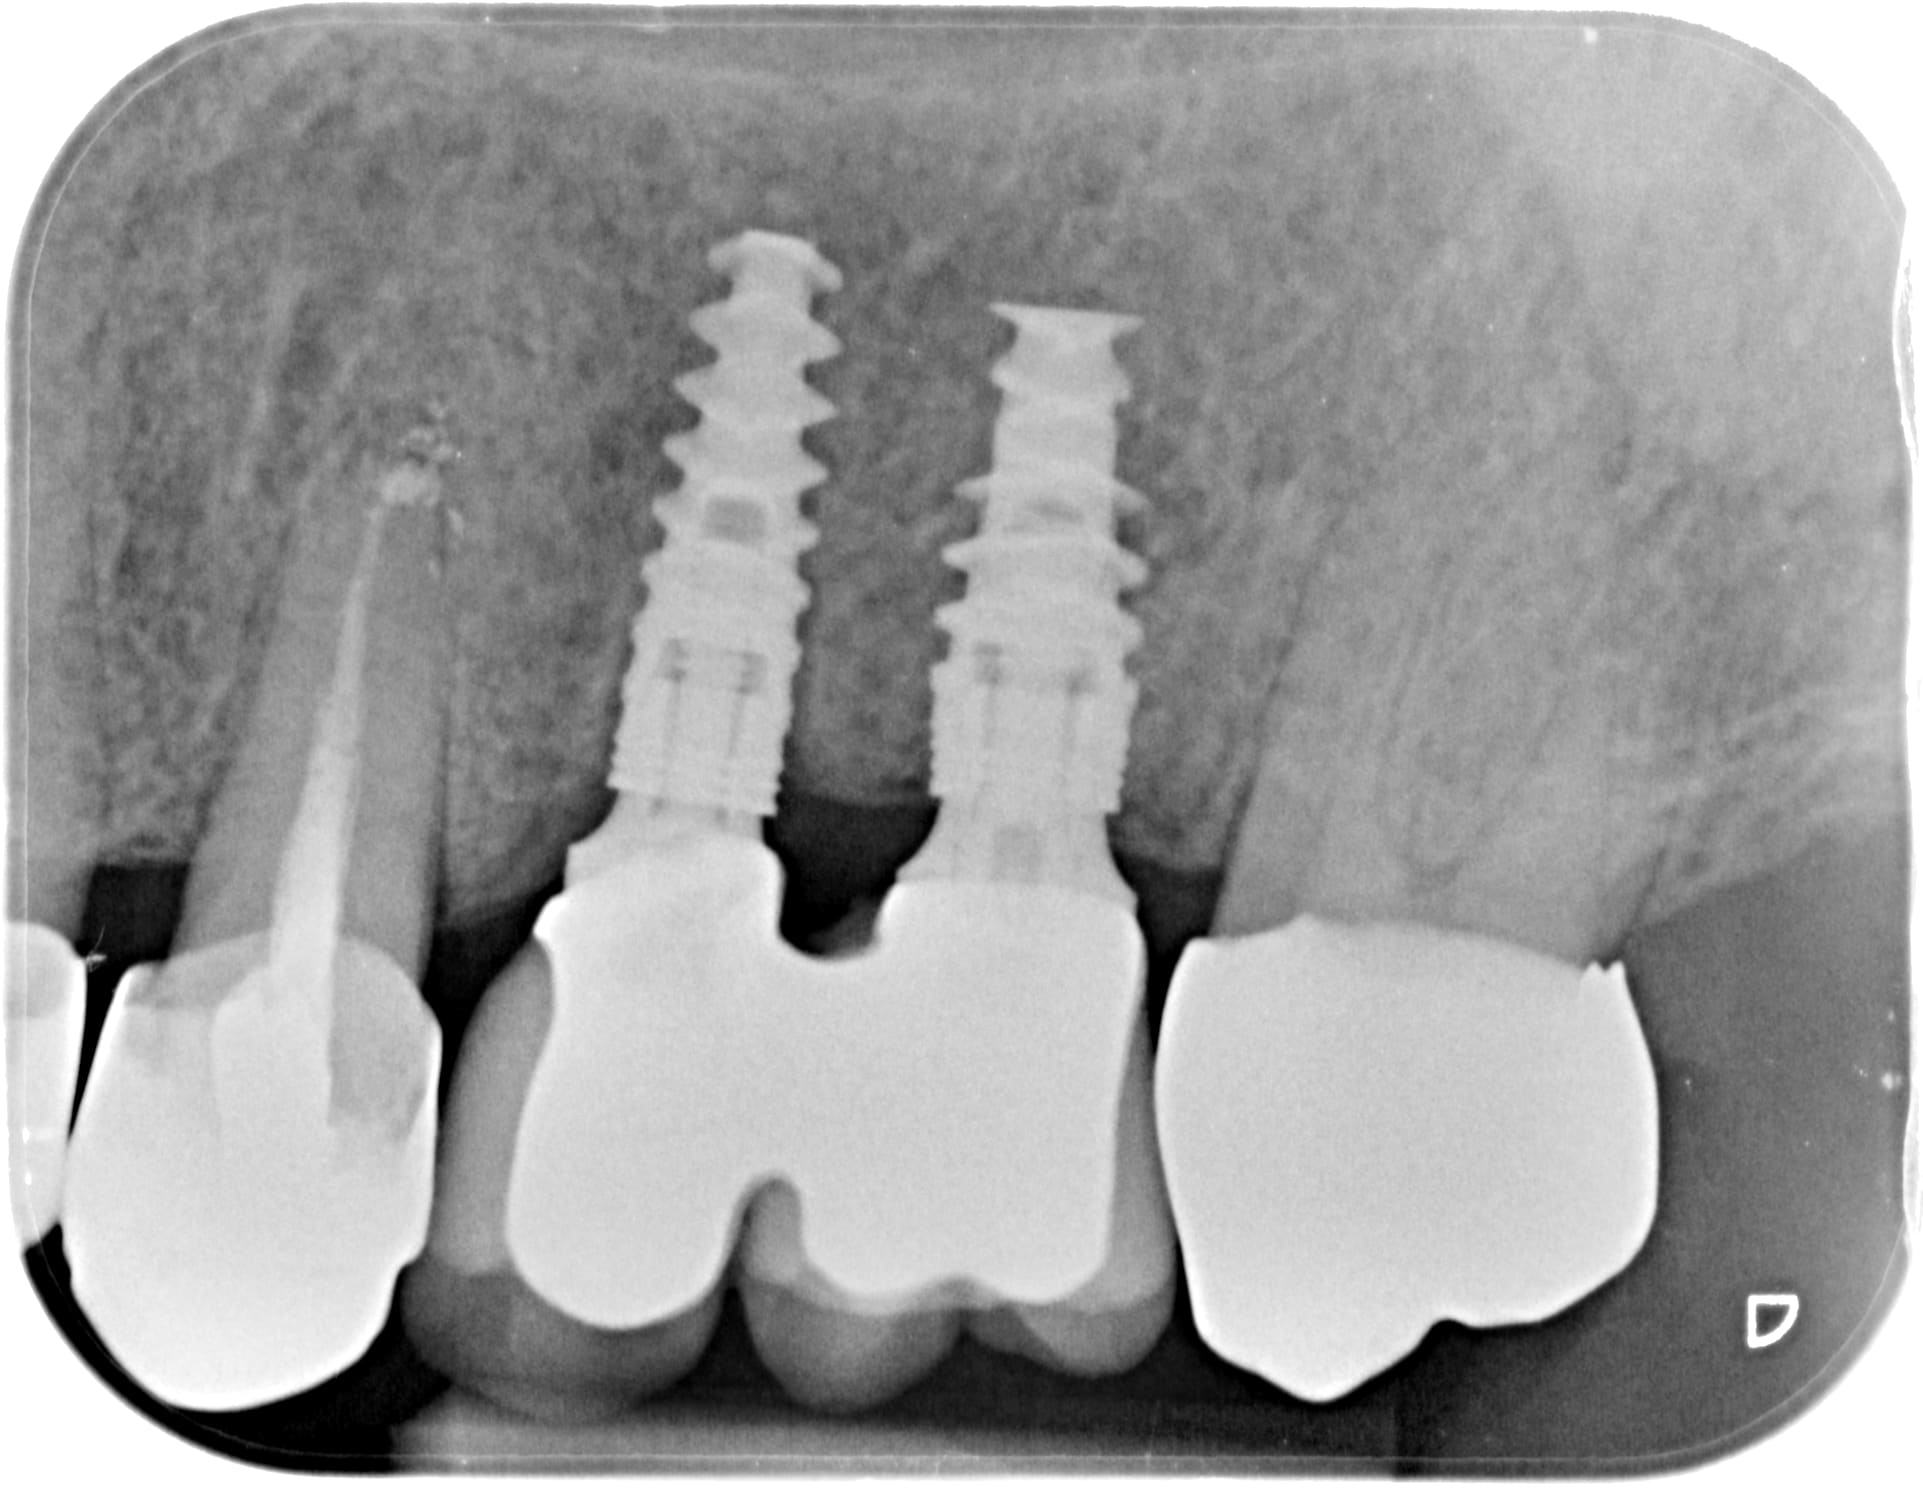

Je pose 3 dents cette aprem et je posterai la radio post op.

Bref... j'ai posé 3 elts cette aprem... empreinte impregum lite + PEI c'est rentré comme papa dans maman lors de leur première saint valentin...